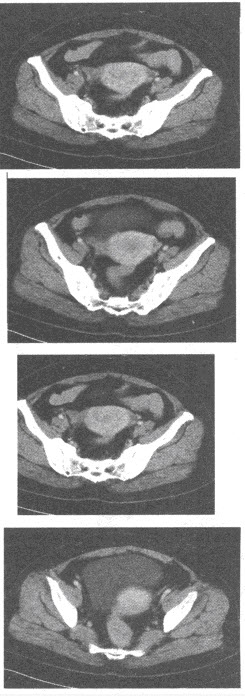

女,65岁,绝经后不规则阴道流血2个月,根据所提供的CT图像,最可能的诊断是()

A:黏膜下子宫肌瘤

B:卵巢浆液性囊腺癌

C:卵巢畸胎瘤

D:子宫内膜癌

E:肌层子宫肌瘤